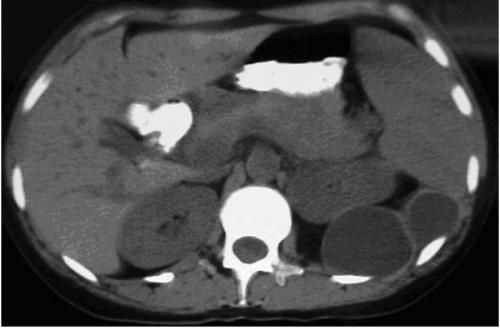

Гидатидозный эхинококкоз вызывает однокамерные образования. Эта болезнь встречается чаще альвеолярной и поражает, прежде всего, печень. В органах и покровах тела эхинококк образует вокруг кист капсулы, наращивая соединительную ткань. В пузырьках постепенно увеличивается количество жидкости. В результате этого они разрастаются, порой до огромных размеров, провоцируя кистозный эхинококкоз. В пузырях развиваются сколексы — так называемый гидативный песок. Его можно обнаружить при КТ-исследованиях на эхинококкоз. Далее возникают дочерние и внучатые кисты, завершая жизненный цикл паразита. Размножение эхинококка и его передача из организма зараженного человека возможно при нарушении целостности пузырей.

ehinokokk na uzi-500x326.jpg

эхинококк на узи